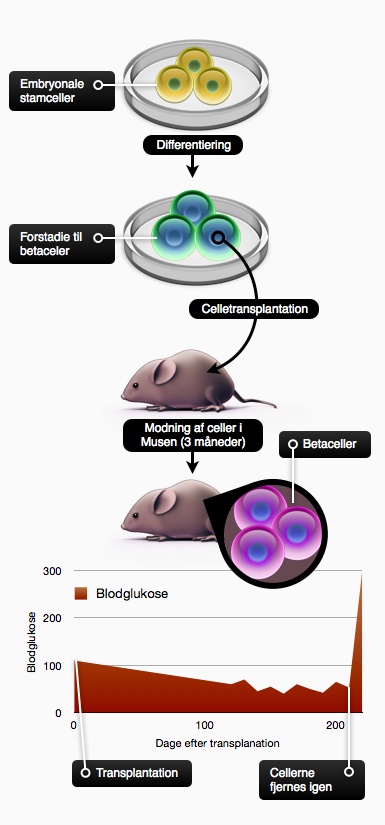

Det er endnu ikke lykkedes forskerne at lave fuldt funktionelle betaceller fra stamceller, men et stort gennembrud kom med transplantationen af stamceller differentieret til celler, der er et forstadie til betaceller. Cellerne er således differentieret til det stadie hvor de udtrykker neurogenin3, hvilket svarer til cellerne i et 6-9 uger gammelt foster. Det er endnu ikke lykkedes forskerne at finde de signalstoffer, der kan lave neurogenin3-positive celler om til betaceller. Cellerne i deres umiddelbare form, udviste kun meget få ligheder med betaceller, og kunne ikke bidrage til at opretholde et normalt blodsukker. Alligevel indopererede forskerne cellerne i mus med diabetes. Det viste sig, at cellerne modnede i musen, og efter 3 måneder var de differentierede til funktionelle menneske-betaceller. Det vil altså sige, at de udifferentierede celler der indsprøjtes, påvirkes af de signalstoffer, der findes i musen. Herefter differentierer de sig i den rigtige retning: til betaceller. Cellerne, der var et forstadie til betaceller, kunne altså bruges til at helbrede musen for diabetes.

Som tidligere beskrevet (se Celleterapi og udviklingsbiologi) skal det være helt sikkert, at den terapeutiske cellekultur, der indsprøjtes, ikke indeholder nogen stamceller. I dette forsøg fik 10-15% af forsøgsmusene kræft, hvilket tyder på, at der har været udifferentierede stamceller blandt de indsprøjtede terapeutiske celler. Samtidig tydeliggør det behovet for at lave fuldt differentierede betaceller i stedet for disse udifferentierede celler.

Figur 34. Umodne forstadier til betaceller kan helbrede diabetes i mus. Stamceller differentieres til neurogenin3-positive celler, der indsprøjtes i portalvenen i mus. Cellerne modner bl.a. til betaceller i musen, hvilket helbreder den for diabetes. Af grafen ses, at blodglukosen falder eftersom de umodne celler modnes til betaceller. Blodglukosen stabiliseres og de små udsving er normale og skyldes måltider m.m. For at vise at det virkelig var de indsprøjtede celler, der helbredte musen, fjernedes de igen, hvorefter blodglukosen som ventet steg dramatisk. Kilde: C. Ricordi & H. Edlund: Toward a renewable source of pancreatic beta-cells. Nature Biotechnology 26, 397–398 (2008).